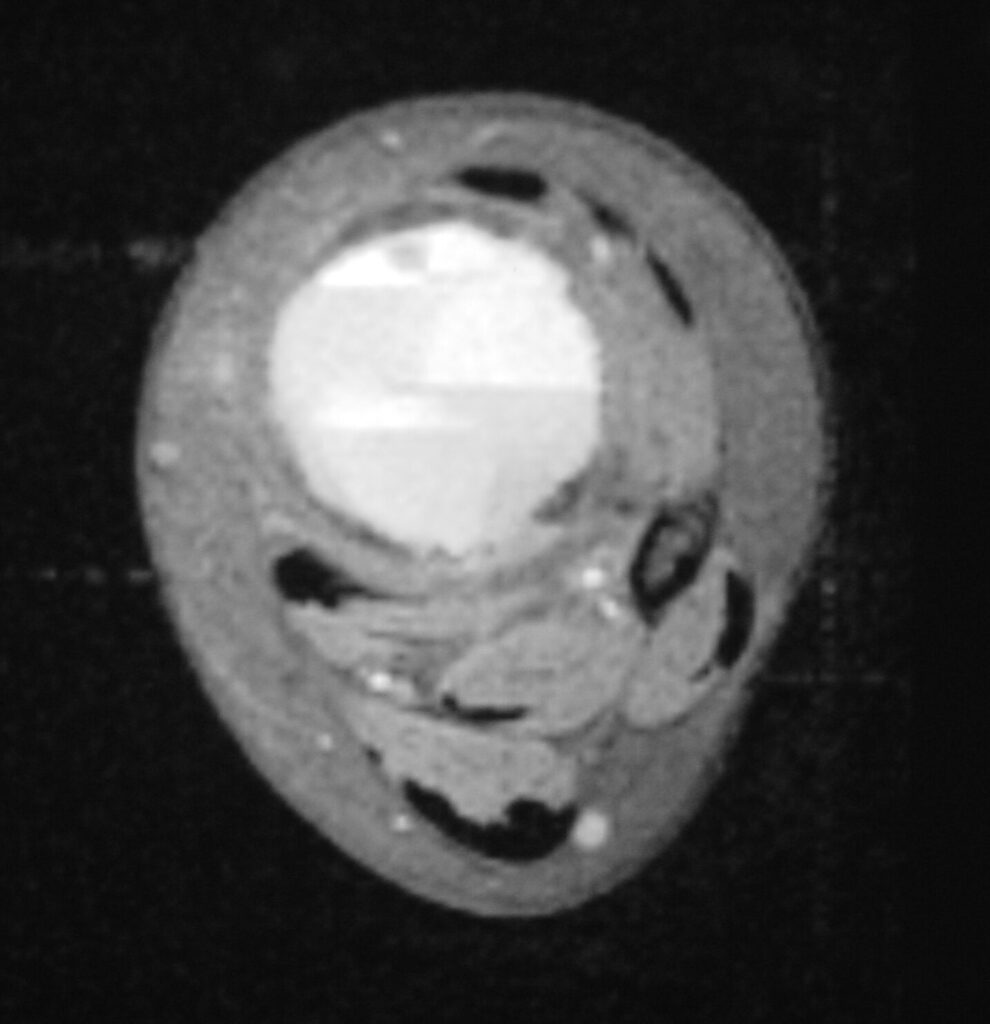

Fig 2 a-e. MRI of an ABC of Distal Tibia: Fig 2 a-c: geographic cystic expansile lesion with fluid-fluid levels. The fluid-fluid levels are caused by bleeding into the cavities. The blood collects and the degredation products settle to the gravity dependent areas of the cavities. This shows up as fluid-fluid levels on the MRI. Fig 2 d,e: This is a gadolinium enhanced MRI of the ABC of the distal tibia. There is peripheral and septal enhancement indication cyst formation. The contrast outlines the cystic cavities but does not enter into the center

Fig 2c: Axial T2 weighted MRI of an ABC